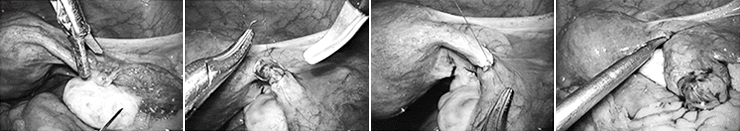

• 미세난관 복원수술

과거에 피임 목적으로 양측 나팔관 결찰술을 시행 받은 여성이 임신을 다시 원할 때 복강경하 미세 수술로 난관이 결찰된 부위를 절제하고 난관을 다시 문합해 난관의 기능을 회복시켜 주는 수술입니다.

미세한 봉합사를 사용하고 복강 내에서 난관의 여러 층을 정확하게 문합 해야 하기 때문에 복강경 술기 중에서도 가장 고도의 수술 능력을 요구하는 수술입니다. 차병원 여성의학연구소는 전세계적으로 가장 많은 난임 관련 수술 경험과 임신 성공율을 보여주고 있습니다.

난관이 정상적으로 복원되면 자연임신도 시도할 수 있고, 체외수정 시술 시 과배란유도 후에 발병할 수 있는 난소과자극증후군, 다태임신을 피할 수 있는 장점을 가지고 있어, 선별적으로 잘 시행한다면 난관 결찰 후 추후 임신을 원하는 경우 아주 효과적인 방법이 될 수 있습니다.